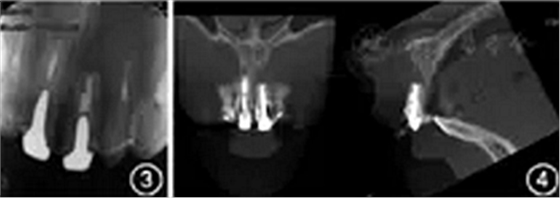

根尖X线片示根管中部以上可见高密度桩核影像,根充欠填,根尖有外吸收,根尖周低密度影。根管中上段无明显显影,结合临床检查判断为纤维桩,根充欠填,根尖周未见明显低密度影(图3)。锥形束CT显示根尖约4 mm×3 mm透影区,根尖部唇侧骨板缺损。根尖可见约1 mm×2 mm透影区,唇侧骨板完整(图4)。根尖未见明显低密度影。1年前根尖X线片显示根充欠填,根尖低密度影,牙冠完整,根尖无异常(图5)。

图3 患者上前牙根尖X线片显示,根尖外吸收,根尖周低密度影;根尖未见明显低密度影;根充欠填,根尖周未见明显低密度影

图4 患者上前牙锥形束CT截面影像显示,根尖可见低密度影,根尖唇侧骨板缺损

图5 患者1年前根尖X线片显示根充欠填,根尖低密度影,牙冠完整,根尖无异常